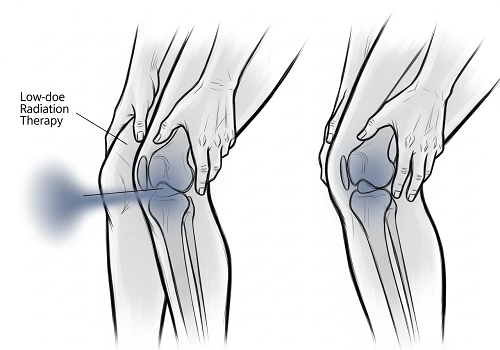

آرتروز شایعترین شکل آرتروزه و وقتی اتفاق میفته که غضروفی که از مفاصل محافظت میکونه، ساییده میشه. این دردناک و ناتوانکنندهست، ولی یه تحقیق جدید میگه که پرتودرمانی با دوز پایین (LDRT) ممکene به عنوان یه راهکار عمل کنه. محققای سراسر کره جنوبی یه کارآزمایی بالینی رو با شرکت ۱۱۴ نفر مبتلا به آرتروز زانو

آرتروز شایعترین شکل آرتروزه و وقتی اتفاق میفته که غضروفی که از مفاصل محافظت میکونه، ساییده میشه. این دردناک و ناتوانکنندهست، ولی یه تحقیق جدید میگه که پرتودرمانی با دوز پایین (LDRT) ممکene به عنوان یه راهکار عمل کنه.

محققای سراسر کره جنوبی یه کارآزمایی بالینی رو با شرکت ۱۱۴ نفر مبتلا به آرتروز زانو انجام دادن تا دو تا دوز مختلف LDRT و یه درمان ظاهری، که هیچ تشعشع واقعیای نداشت، رو با هم مقایسه کنن. شرکتکنندهها نمیدونستن تو کدوم گروه هستن.

اونایی که دوز بالاتر LDRT رو، که در طول شش جلسه داده میشد، دریافت کرده بودن، بهبودهای خیلی بیشتری رو تو درد، عملکرد فیزیکی و وضعیت کلیشون، در مقایسه با دو تا گروه دیگه، گزارش دادن (هرچند که یه سری شواهد از اثر دارونما هم وجود داشت).

این غضروف رو تو آرتروز شدید، که تو اون بافت همین الانش هم از بین رفته، بازسازی نمیکونه، ولی LDRT به عنوان راهی برای مدیریت علائم و قابل تحملتر کردن آرتروز، امیدبخش ظاهر شده. تستهای بیشتری هم برنامهریزی شده تا ببینن آیا هیچ تغییری تو ساختار مفصل هم به وجود میاد یا نه.

بخشی از دلیلی که هنوزم یه کم عدم قطعیت در مورد LDRT برای آرتروز وجود داره، به خاطر ضررهاییه که تشعشع میتونه ایجاد کنه، اگه به درستی مدیریت نشه. دوزهایی که اینجا داده شدن، کمتر از ۵ درصد از اونایی بودن که معمولاً برای درمانهای سرطان داده میشن و به گفته محققها، هیچ عارضه جانبی مرتبط با تشعشعی توسط شرکتکنندههای این تحقیق گزارش نشد.

کیم میگه: «یه تصور غلطی وجود داره که تشعشع دارویی، یا درمانی، همیشه تو دوزهای بالا داده میشه. ولی برای آرتروز، دوزها فقط یه کسر کوچیکی از چیزیه که ما برای سرطان استفاده میکنیم و درمان، مفاصلی رو هدف قرار میده که از اعضای حیاتی دور هستن، که احتمال عوارض جانبی رو کم میکونه.»

کیم میگه: «برای آرتروز شدید، که تو اون مفصل از نظر فیزیکی تخریب شده و غضروف همین الانش هم از بین رفته، تشعشع بافت رو بازسازی نمیکونه. ولی برای آدمای با بیماری خفیف تا متوسط، این رویکرد میتونه نیاز به تعویض مفصل رو به تأخیر بندازه.»